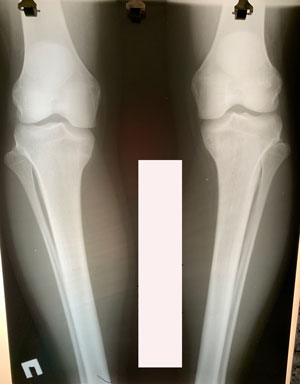

Исходник - 23 года.

Дата операции - 27.01.2021

Вложения

image-27-01-21-10-26-5.jpg

image-27-01-21-10-27.jpg